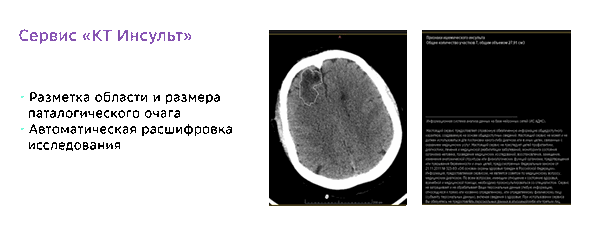

КТ Инсульт: проводит на томограммах поиск областей с острым нарушением мозгового кровообращения;